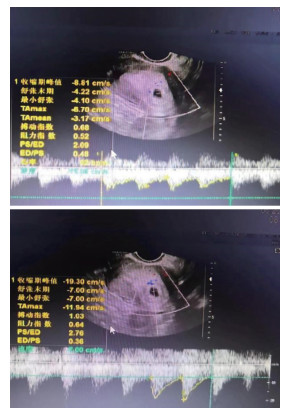

超声动脉血流参数联合血清ACA、AMH检测对先兆流产保胎结局的预测作用

关艳丽, 张丽, 裴丽娟, 张梅

2025, 23(10): 1748-1752. doi: 10.16766/j.cnki.issn.1674-4152.004220

1 0

摘要:

目的  先兆流产(TA)经治疗后仍可能出现保胎失败,本研究旨在分析超声动脉血流参数联合血清抗心磷脂抗体(ACA)、抗苗勒管激素(AMH)检测对保胎结局的预测作用,以提高TA保胎成功率。  方法  选取2021年5月—2023年5月黄河三门峡医院及南阳市中心医院收治的135例TA患者,根据保胎结局将其分为保胎成功组(83例)及保胎失败组(52例)。患者均行超声动脉血流参数及血清ACA、AMH检测,采用logistic回归模型分析保胎结局的影响因素,ROC曲线分析超声动脉血流参数和血清ACA、AMH对保胎结局的预测价值。  结果  与保胎成功组比较,保胎失败组舒张末期流速(D)、AMH水平降低,收缩期峰值流速(S)/D、搏动指数(PI)、阻力指数(RI)、ACA水平及自然流产史、阴道出血量≥50 mL占比升高(P < 0.05);Logistic回归分析结果显示,阴道出血量≥50 mL、S/D、PI、RI及ACA高水平均为TA保胎失败的独立危险因素(P < 0.05,OR>1),AMH高水平为保护因素(P < 0.05,OR < 1);ROC分析结果显示,S/D、PI、RI、ACA及AMH单独及联合预测保胎结局的AUC分别为0.724、0.676、0.752、0.755、0.692及0.880,五项联合预测效能高于各项单独检测。  结论  TA患者超声动脉血流参数异常,其中S/D、PI、RI、ACA高水平是TA保胎失败的危险因素,AMH高水平为TA保胎失败的保护因素,五项联合检测对于TA保胎结局具有较高的预测价值。